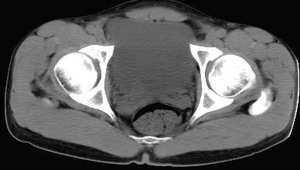

男,25岁,尿血15天,bus示膀胱内囊性占位

第1\\2图可见右侧输尿管扩张积水,第四\\五图膀胱内右侧精囊腺前方可见枣核样囊影,壁薄均匀,内为水密度.bus和ct均诊断:右侧输尿管末端囊肿,已建议ivp.